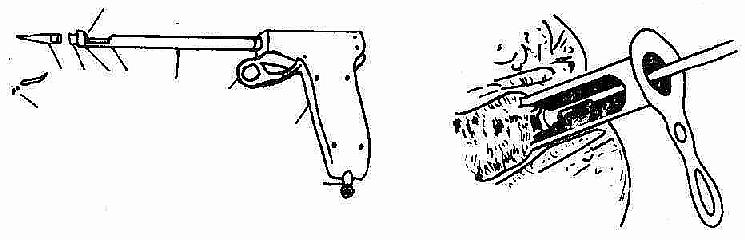

2.胶圈套扎法 将特制的0.2~0.3cm宽的乳胶圈套在痔根部,使痔缺血坏死脱落,术后有继发出血的可能。如无套扎器(图2-110A),也可用两把止血钳替代(图2-110B)。

A.器械 B.痔被吸入,胶圈套住基底部

图2-110A 器械套扎法

1.乳胶圈2.扩胶圈圆锥体3.套扎圆筒4.套扎推圈5.空心管

6.套管 7.扳手 8.手柄 9.空心管(接吸引器) 10.玻璃片

图2-110B 内痔胶圈套扎术